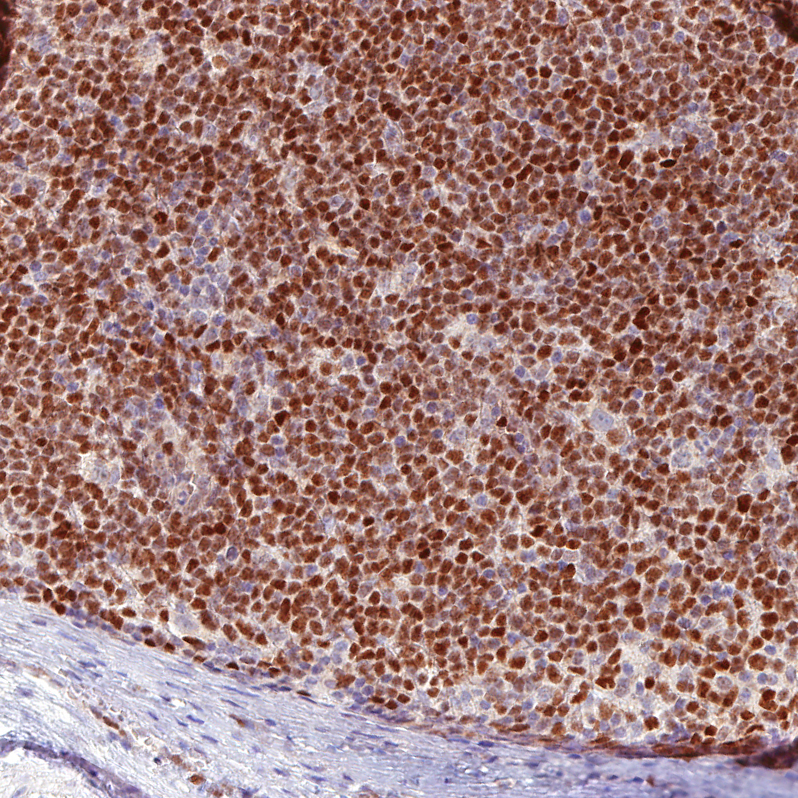

Immunohistochemical staining of human mantle cell lymphoma shows moderate to strong nuclear positivity in tumor cells.